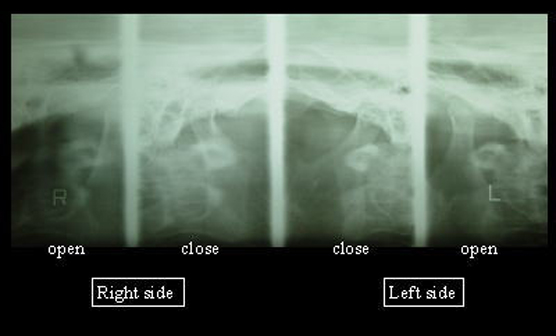

4.顎関節レントゲン

顎関節の形態の変化や運動量を調べます。